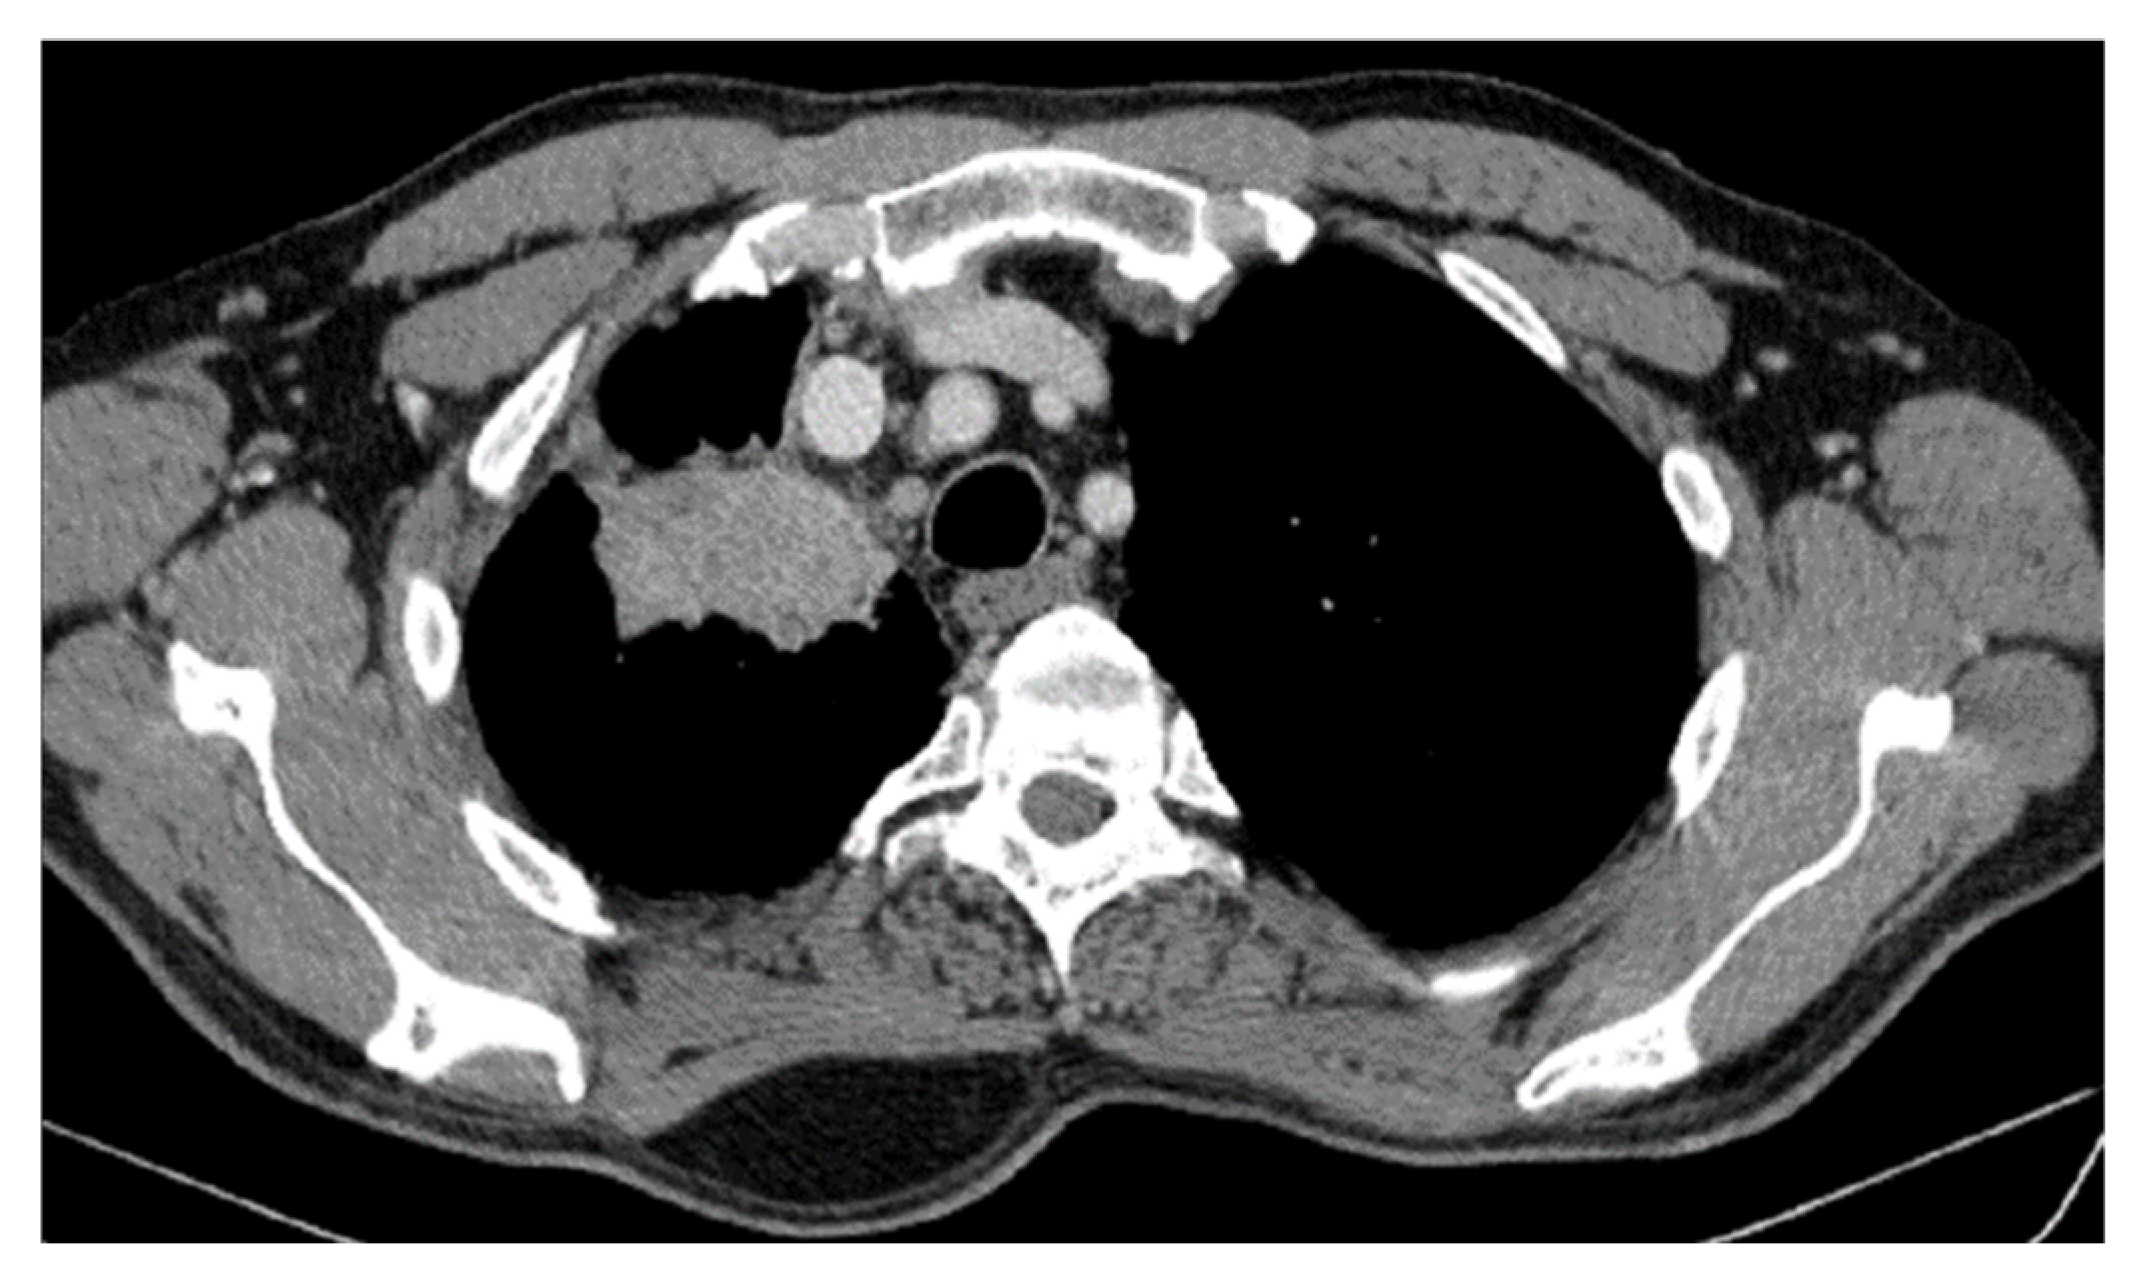

2. Case Presentation

2.2. Monitoring 2022: Oncological Commission 1910/16.08.2022

2.3. Oncological Committee 07/25/2023 Recommended

- Consider rescue re-irradiation (SBRT), taking into account the current primary tumor dimensions of 24 × 34.2 mm on PET CT from 06/2023 and also the total dose previously administered (08–09/2020), the previously applied fractionation, the time between the two irradiations, the cellular repair time and the dose constraints for the organs at risk.